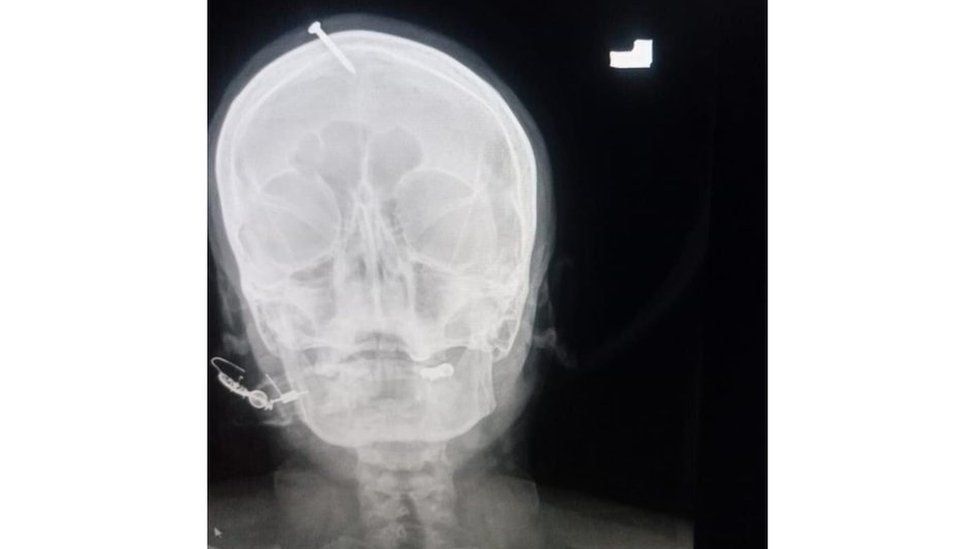

Paku menancap di kepala perempuan hamil/Istimewa

Islamabad: Otoritas Pakistan memburu dukun yang menancapkan paku ke kepala perempuan yang tengah hamil. Staf Rumah Sakit Lady Reading Haider Khan mengatakan perempuan itu meminta bantuan dukun untuk melahirkan anak laki-laki.

Ibu dari tiga anak yang tengah hamil itu meminta bantuan dukun lantaran diancam bakal ditinggal suaminya jika melahirkan anak perempuan lagi. Khan mengatakan perempuan itu dalam kesakitan yang luar biasa.

Kepala polisi Peshawar Abbas Ahsan membentuk tim investigasi untuk memburu dukun tersebut. Pihaknya telah menginterogasi pihak rumah sakit dan mencari perempuan hamil yang telah meninggalkan rumah sakit setelah dokter mencabut paku dari kepalanya.